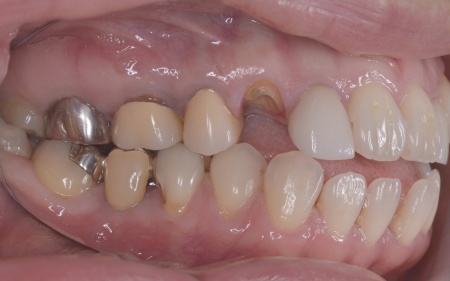

| カウンセリング | 拝見したところ、左下と右上の歯はともに大きな虫歯があり、歯だけでなく被せ物を支える土台の部分にも影響が及んでいました。

さらに、ほかの歯に入っている詰め物や被せ物の周囲にも、過去に治療した部分に再び虫歯ができる二次カリエスが複数見つかりました。 また、噛み合わせを確認したところ、奥歯で噛み合わせた際に上下の前歯が当たらず隙間ができる開咬(かいこう)が認められました。 実際に患者様の場合も、特定の歯に長期間強い力がかかり続けたことで歯や修復物の破損、さらには口腔内全体のトラブルにつながった可能性が高いと考えられました。 修復治療が必要でしたがこの噛み合わせの問題を改善しないまま行うと、治療した歯に再び過度な力が加わって被せ物の破損・脱離や虫歯の再発を招くリスクが高まります。 |

まずは矯正治療を優先し、噛み合わせが整ってから虫歯の再発リスクの低いセラミックの被せ物・詰め物などで歯の形態と機能を回復する方針を提案し、同意いただきました。

矯正治療については、専門的な診断と管理が必要と判断したため専門の矯正歯科医院をご紹介し、他院にて実施していただきました。 矯正治療終了後、改めてお口の中を確認したうえで、歯の状態に合わせ虫歯の除去や土台の修復を丁寧に行い、精密な型取りを実施しています。 最後に噛み合わせ全体のバランスを確認しながら新しく作製した被せ物や詰め物を装着し、見た目に問題がないか、噛み合わせが安定しているかを確認し、治療を終了しました。 |